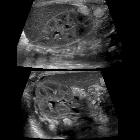

Ultrasound

Generally, fungal balls are appreciated as mobile, rounded, heterogeneously hypoechoic masses, although hyperechoic masses have also less frequently been described . No evidence of vascularity is seen within the mass on a Doppler study .